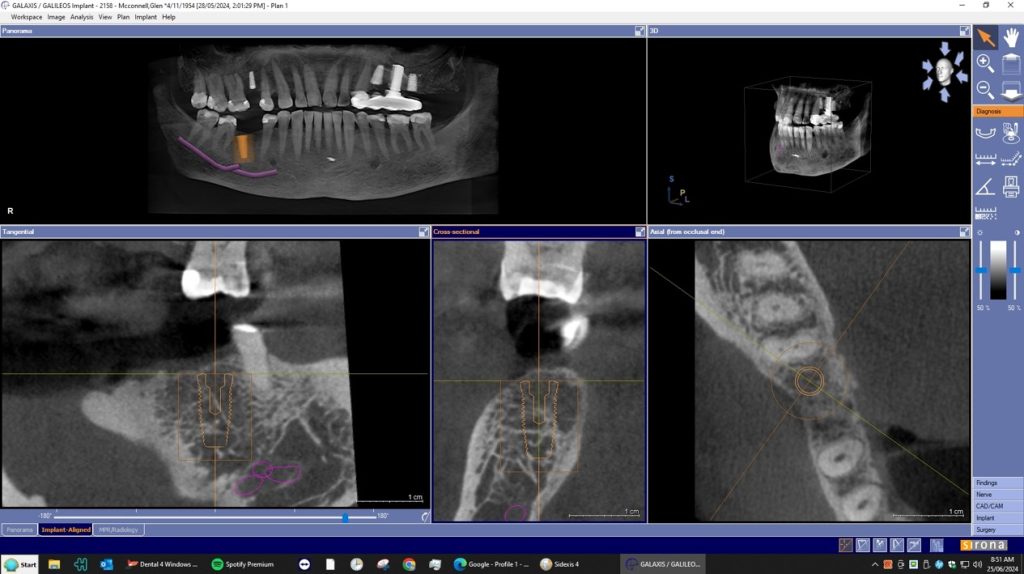

A dental Implant is a titanium “root” that integrates directly with the surrounding bone and replaces the function of the natural tooth. Neoss Implants are made using the best quality medical grade titanium, which is well known for its proven biocompatibility, and have a treated surface to facilitate bone integration.

The aim is to improve your health, chewing function and/or aesthetic appearance and once healing and restoration is complete you will be able to enjoy a wide variety of foods again.